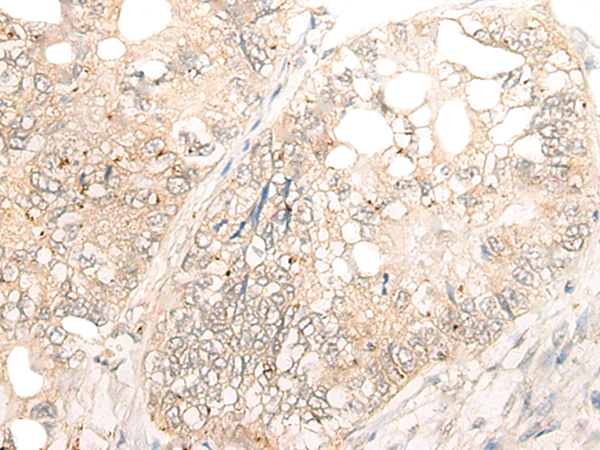

IHC positive control: |

Human thyroid cancer and Human esophagus cancer |